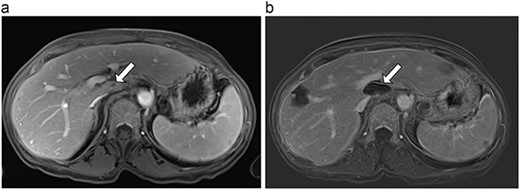

(a) Pre-ablation MRI demonstrating 5 mm lesion in caudate lobe of liver. (b) Post-ablation MRI (19 days postoperatively) demonstrating 36.2 mm complete ablation of caudate lesion.

| 3 (5a,b) | 68, F | Colon adenocarcinoma | 6 cycles modified FOLFOX-6 | 8 | Laparoscopic microwave ablation and low anterior resection of colon | 5 | 36.2 | 31.2 | 15 | No |